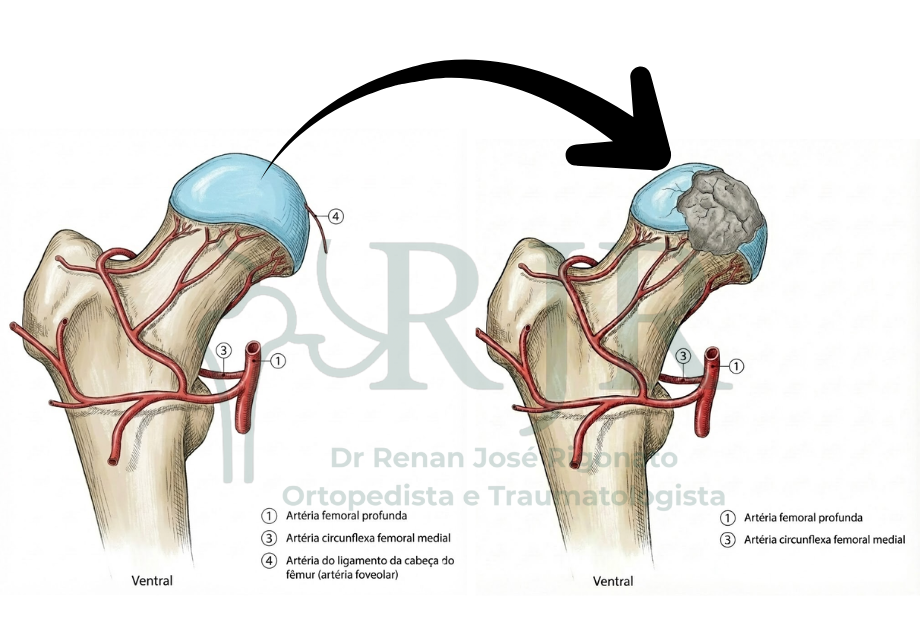

A cabeça do fêmur depende quase exclusivamente de uma única fonte de irrigação sanguínea: a artéria circunflexa femoral medial, que se origina da artéria femoral profunda. Essa artéria é responsável pela maior parte do suprimento sanguíneo da cabeça femoral, especialmente do osso subcondral, fundamental para a sustentação da articulação do quadril.

Por haver pouca circulação alternativa, qualquer situação que reduza ou interrompa o fluxo dessa artéria pode levar à diminuição crítica da irrigação do osso, favorecendo o desenvolvimento da osteonecrose da cabeça do fêmur.